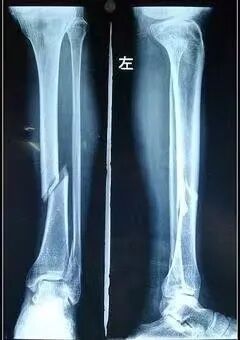

由于胫骨或腓骨骨折,尤其是腓骨近端骨折,膝关节可能会损伤腓总神经。胫骨平台骨折的腓神经损伤发生率约为1%。利用后外侧切口并放置牵开器以保护神经免受牵拉有助于预防关节镜膝关节手术期间的腓总神经损伤(Epps et al., 1994)。